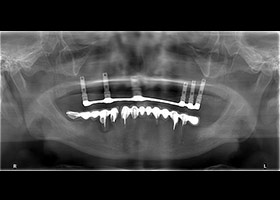

![proimages/case/Artificial_implant/HON01.jpg proimages/case/Artificial_implant/HON01.jpg]()

1. 病患最初全口X光片。